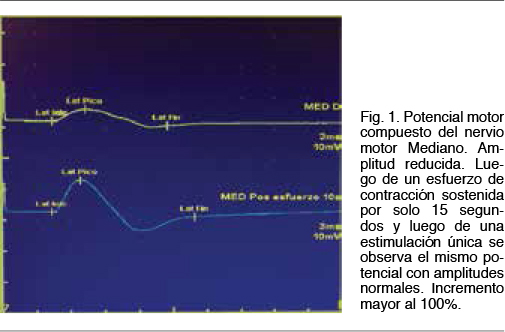

Se observa una neuroconducción sensitiva con latencias distales, amplitudes y velocidades de conducción normales. El electromiograma fue normal. Del estudio de neuroconducción motora destacamos la presencia de potenciales motores bien configurados, de latencias normales, con velocidades de conducción motora normales y sin bloqueos de la conducción, pero con amplitudes reducidas en 4 miembros. Se realiza una breve contracción isométrica de 15 segundos y se procede a la estimulación motora nuevamente, observandose un incremento de la amplitud a rangos normales. El incremento de amplitud obtenido fue > 100% para nervio motor Mediano (Figura 1). En el estudio de transmisión neuromuscular repetitiva realizado en el nervio motor Cubital se observa un decremento en el tren de potenciales obtenidos a baja frecuencia (5Hz) en un 33% entre el primer potencial y el cuarto potencial y con una morfología del tren en descenso lineal (Figura 2). El cociente de decremento tardío / decremento temprano fue de 102%. A alta frecuencia (30Hz) se observo un incremento de la amplitud de un 635% entre el primer potencial y el potencial número 100 (Figura 3).